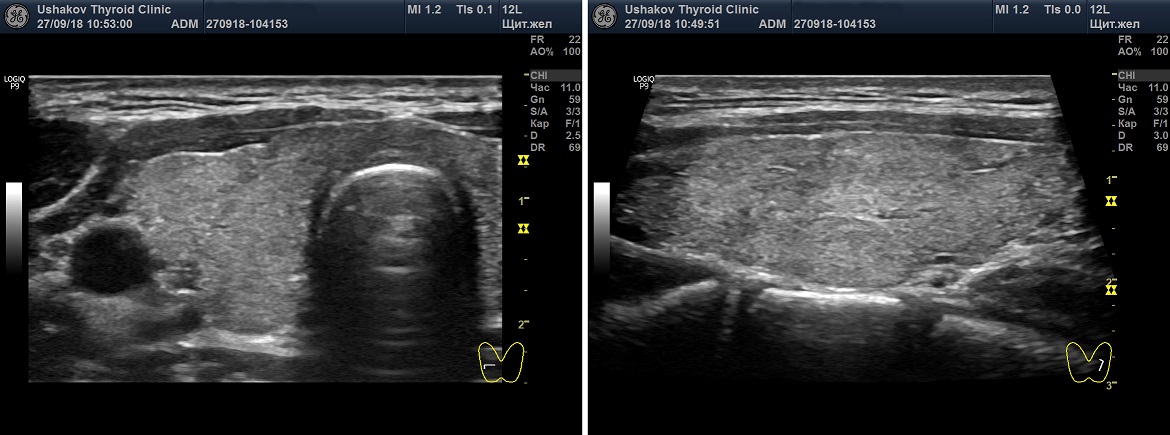

Допустим, врач правильно настроил допплеровские параметры своего УЗ-аппарата (в зависимости от настроек интенсивность кровотока может оказаться разной). Врач должен раздвинуть на своем видимом поле допплеровскую карту максимально широко, охватывая всю видимую часть ЩЖ. Попытка определить интенсивность кровотока в маленьком допплеровском окошке усложнит процесс и может способствовать ошибке.

Рисунок 3. Разные настройки режима ЭДК ультразвукового допплеровского исследования. Представлена одна и та же проекция правой доли щитовидной железы. Период между снимками ― 1 минута. Слева ― с нормальными базовыми настройками (смотрите справа значения PRF), справа ― с настройками более высокой чувствительности. Видно, что при изменении настроек определяется не нормальный, а усиленный кровоток.